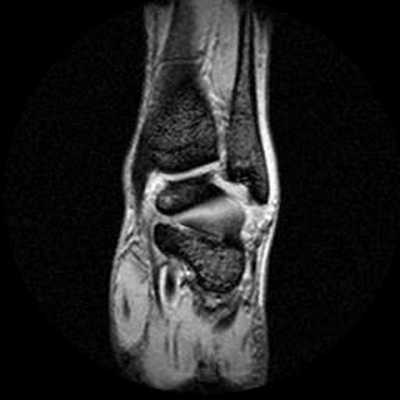

4. МРТ при переломе тела и отростков таранной кости:

• Если перелом в свое время не был замечен, пациенты могут быть направлены на МРТ уже по поводу хронических болей

5. МРТ при фрагментировании суставных поверхностей голеностопного сустава:

• Выявляемые изменения в достаточно высокой степени коррелируют с хирургическими критериями классификации Берндта и Харти (стадии 1-5):

о Существуют некоторые различия, обусловленные длительностью повреждения

• Отек костного мозга может быть выявлен на любой стадии повреждения:

о Распространяется от суставной поверхности радиально

о Гипоинтенсивный сигнал на Т1 ВИ, гиперинтенсивный сигнал на Т2 ВИ, в режиме STIR

о Выраженность отека со временем уменьшается, и в хронической фазе он может исчезнуть

• В хронической фазе может наблюдаться репарация суставного хряща в области дефекта:

о Однако при артроскопии в области дефекта будет выявляться патологический суставной хрящ

о Даже если суставной хрящ при МРТ будет выглядеть целым, диагноз можно поставить по наличию изменений костной ткани

• Стадия 1:

о Снижение интенсивности сигнала на Т2 от суставного хряща или наличие в хряще дефекта

• Стадия 2:

о Серповидная линия перелома проходит в субхондральном отделе от одного до другого края кости

о ± снижение интенсивности сигнала на Т2 от суставного хряща

о ± ограниченный дефект суставного хряща

о ± отек костного мозга

• Стадия 3:

о Признаки второй стадии + наличие жидкости или контрастного препарата между костно-хрящевым фрагментом и материнской костью

• Стадия 4:

о Вогнутый дефект суставной поверхности

о ± свободный фрагмент в полости сустава

• Стадия 5:

о «Киста» с четким контуром:

- Гипоинтенсивный сигнал на Т1 ВИ, гиперинтенсивный сигнал на Т2ВИ

- Часто наблюдается контрастное усиление «кисты», поскольку она заполнена фиброзной тканью

- Вокруг может определяться различной выраженности отек костного мозга